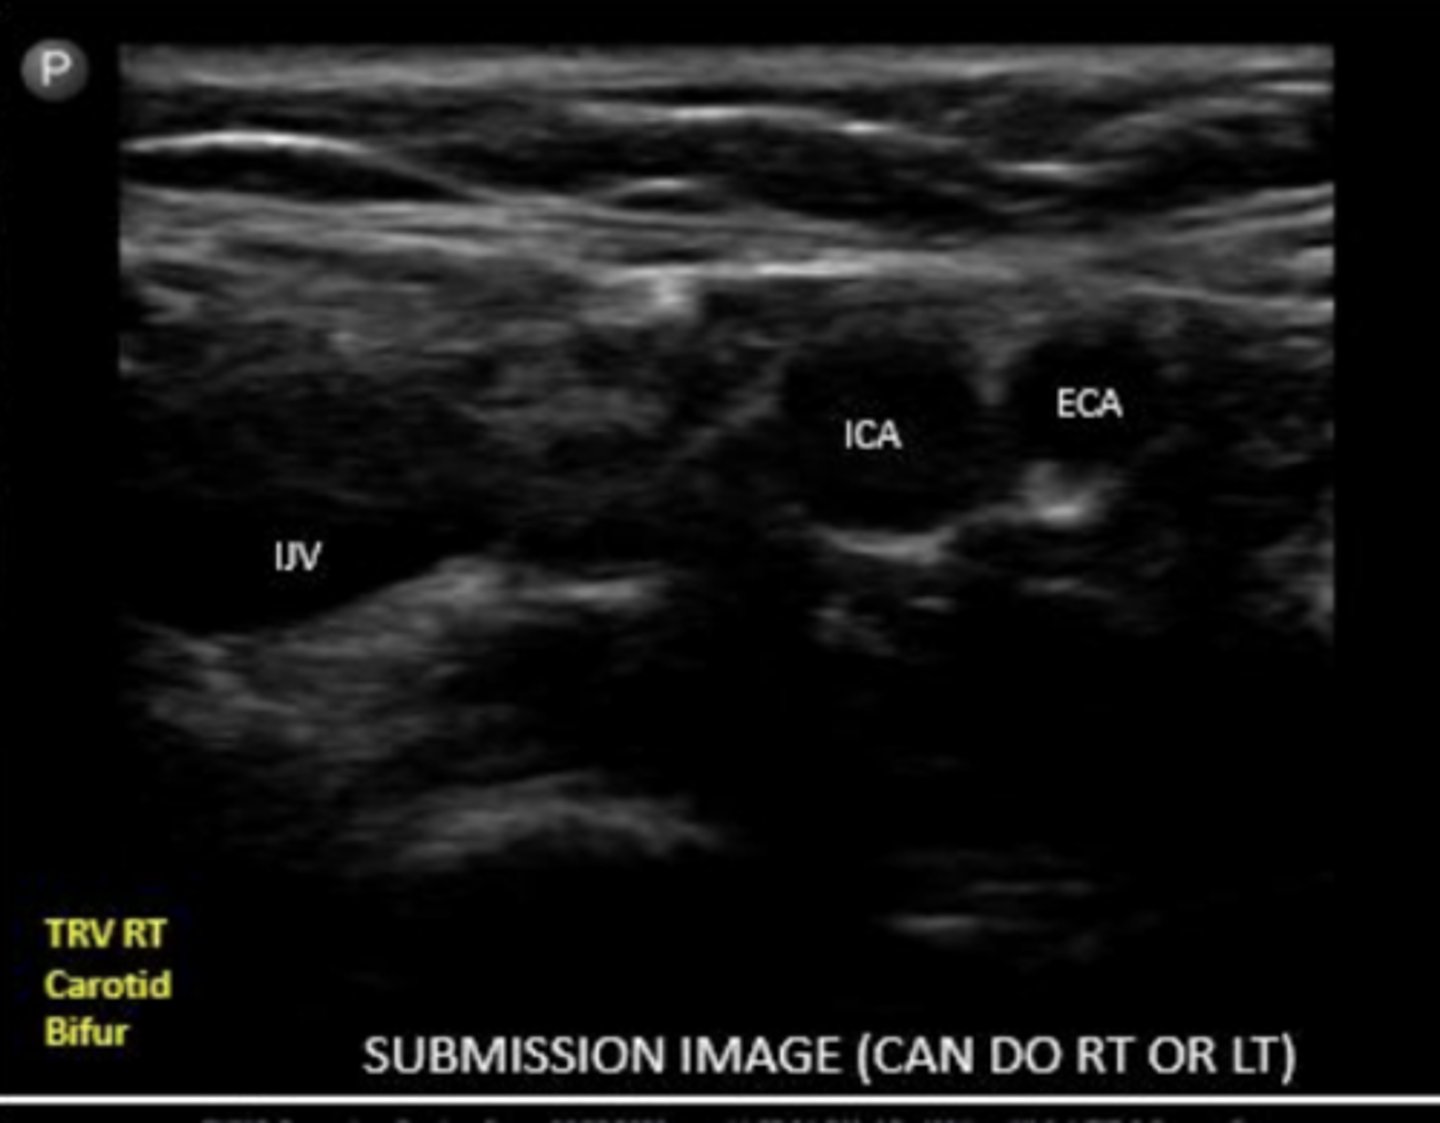

what will you see before the bifurcation into ECA and ICA

carotid bulb

ICA

internal carotid artery

ECA

external carotid artery

ECA is typically more _____ and ______

ECA is usually more anterior and medial

ICA is typically more ____ and _____

ICA is usually more posterior and lateral

When scanning the carotid bifurcation, is the IJV the most medial or lateral structure?

lateral

How can you distinguish between ICA and ECA on US?

use color and pulsed wave flow